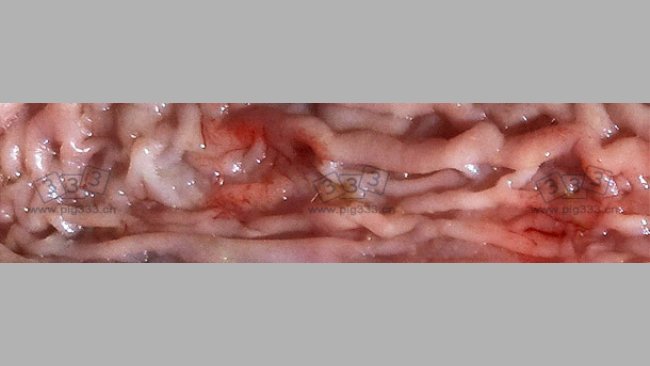

神经症状主要表现是部分仔猪脑膜炎、眩晕,大量仔猪表现出精神不振和抑郁。所有剖检病猪都有严重的肺部充血、轻重不一的肠炎和肠系膜淋巴结感染。